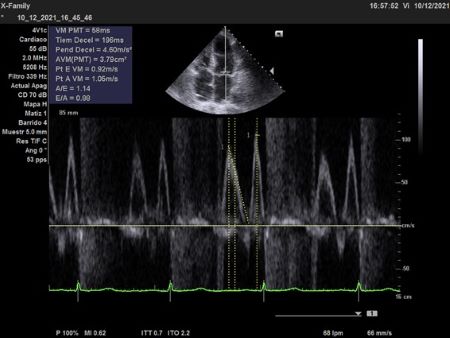

Doppler continuo a través de la Válvula pulmonar. En la imagen, se observa el Doppler continuo a través de la válvula pulmonar: en sístole presenta una velocidad máxima de 1,6 m/seg; levemente incrementada dado el hiperflujo. El tiempo de aceleración es de 157 ms. En diástole presenta un reflujo denso, de igual intensidad al flujo sistólico, de morfología triangular. Corto en duración, proto – mesodiastólico, finaliza 190 ms previo al inicio de la sístole siguiente. El tiempo de hemipresión es de 74 ms. El índice de regurgitación pulmonar es de 0.59. Los hallazgos son concluyentes con un reflujo severo.

Doppler pulsado transmitral. El perfil de lleno transmitral es de relajación prolongada. No se observa hiperflujo. Velocidad de onda E 0,92 m/seg. Relación E/e’ 9.

Doppler continuo transmitral. El Doppler continuo transmitral muestra que la insuficiencia es holosistólica, el espectro tiene forma de parabola y no es denso.

El Doppler color muchas veces subestima la severidad de la insuficiencia pulmonar (IP), dado que el reflujo finaliza tempranamente en la diástole, siendo la duración del reflujo inversamente proporcional a la severidad.

El dato más útil para el estudio de la IP es el Doppler continuo.

Una señal regurgitante densa y triangular, que finaliza previo al inicio del flujo anterógrado denota severidad. Al igual que un

índice de regurgitación pulmonar (relación entre la duración del reflujo y el intervalo entre dos flujos anterógrados) menor a 0,77 y un tiempo de hemipresión menor a 100 ms.